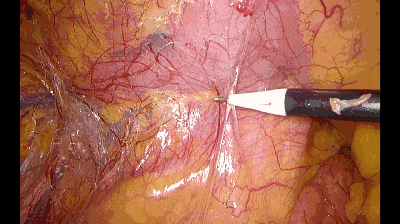

一、推钩:

利用钩的钝性推开组织间的粘连,创造游离平面,犹如轻轻推开一扇窗。